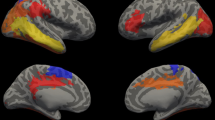

Cortical morphological differences between groups were distributed throughout the right caudal middle frontal gyrus, right fusiform gyrus, right lateral occipital gyrus, right precuneus, and left inferior parietal lobule. Among children with tetralogy of Fallot, altered cortical structures were correlated with the visual spatial index, working memory index, and perioperative variables.